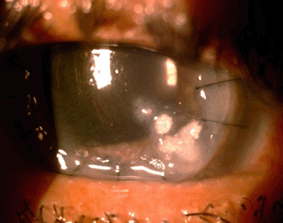

Figure 1. Fungal corneal ulcer